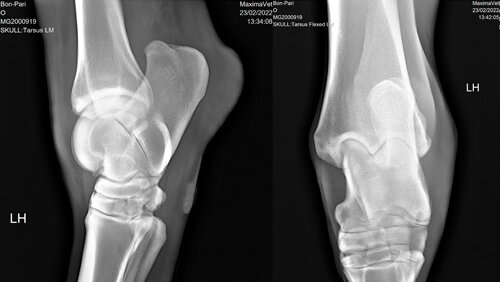

Проекции рентгена

Рентгенография – это вид лучевой диагностики, который позволяет визуализировать состояние внутренних структур организма. Идея исследовать ткани и органы при помощи рентгеновских лучей возникла более ста лет назад. Сегодня рентгенография – один из самых распространённых методов диагностики. Больше интересных статей на нашем сайте Рентгеновская проекция – это изображение трехмерного объекта, например, сустава, на двухмерном листе. Различают прямые, боковые и косые проекции. При съемке в прямой проекции лучи проходят в переднезаднем направлении...